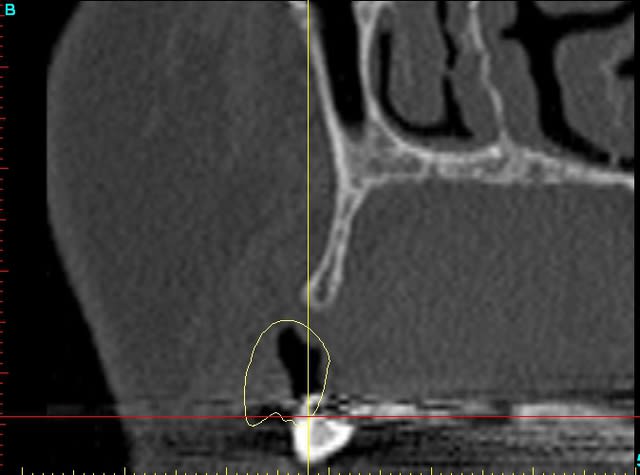

Dar12 dmdcf3 - Eugenol

Dar13 snfr77 - Eugenol

14dar tm9a6n - Eugenol

Dar14 mu6ia0 - Eugenol

15dar srylok - Eugenol

23dar fu8chl - Eugenol

Dar23 cngblb - Eugenol

24dar rfsfid - Eugenol

Dar24 scegbz - Eugenol

25dar yv2tvr - Eugenol

Dar15 gpvqe1 - Eugenol

Dar25 mrwngv - Eugenol

12dar ujxzdu - Eugenol

13dar zaa5vz - Eugenol

22dar mrs1pw - Eugenol

Darcl12.12 - Eugenol